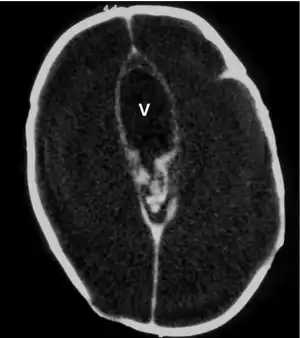

Macrocephaly is a condition in which circumference of the human head is abnormally large.[1] It may be pathological or harmless, and can be a familial genetic characteristic. People diagnosed with macrocephaly will receive further medical tests to determine whether the syndrome is accompanied by particular disorders. Those with benign or familial macrocephaly are considered to have megalencephaly.

Macrocephaly is customarily diagnosed if head circumference is greater than two standard deviations (SDs) above the mean.[11] Relative macrocephaly occurs if the measure is less than two SDs above the mean, but is disproportionately above that when ethnicity and stature are considered. Diagnosis can be determined in utero or can be determined within 18–24 months after birth in some cases where head circumference tends to stabilize in infants.[12] Diagnosis in infants includes measuring the circumference of the child's head and comparing how significant it falls above the 97.5 percentile of children similar to their demographic. If falling above the 97.5th percentile then the patient will be checked to determine whether there is any intracranial pressure present and whether or not immediate surgery is needed.[2] If immediate surgery is not needed then further testing will be done to determine whether the patient has either macrocephaly or benign macrocephaly.

Benign or familial macrocephaly

Benign macrocephaly can occur without reason or be inherited by one or both parents (in which it is considered benign familial macrocephaly and is considered megalencephaly form of macrocephaly). Diagnoses for familial macrocephaly is determined by measuring the head circumference of both parents and comparing it to the child's. Benign and familial macrocephaly is not associated with neurological disorders.[2] While benign and familial macrocephaly does not result in neurological disorders, neurodevelopment will still be assessed.